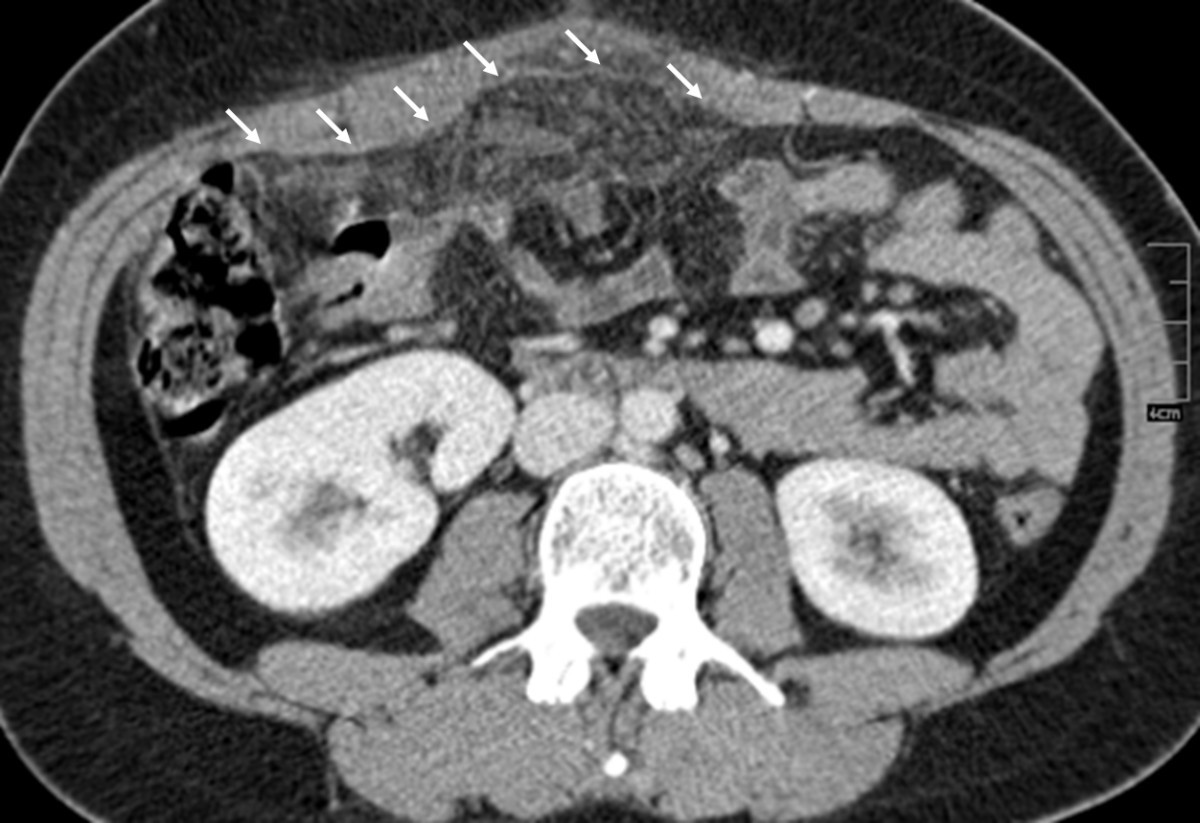

from www.ajkd.org

Peritoneal Dialysis Outflow Failure From Omental Wrapping Diagnosed by